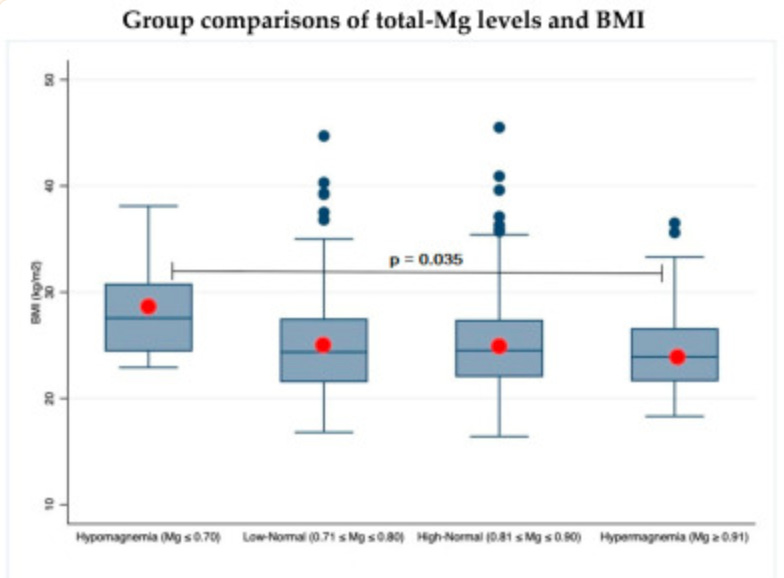

マグネシウム (Mg)と動脈硬化との関連を示す証拠は、これまでのところ相反するものである。代わりに、低マグネシウム血症を伴う高血圧と高体重指数 (BMI)の間の相互作用が、より一貫した方法で文献に記載されている。本研究の目的は、一般集団における血中Mg濃度と血行動態および身体組成パラメータとの相関を再検討し、総Mg (Tot-Mg)と比較してイオン化Mg (Ion-Mg)の感度プロファイルを探索することである。われわれは、既報のスイス人集団から無作為に選んだ755人の被験者からデータを収集し、サンプルをイオン化マグネシウム(全血)と総マグネシウム(血清)に従って4つの等価クラスに層別化した。..

この結果は、血行動態、身体組成パラメータおよびマグネシウム代謝異常との相関を検出する上で、Tot-Mgと比較してIon-Mgは異なるプロファイルを提供することを確認するものであった。 低濃度のマグネシウムは、動脈老化パラメータの悪化、24時間血圧変動幅の拡大、およびBMIの上昇と関連していた。Ion-Mgは血圧との相関のみ検出することに優れていた。イオンMgはマグネシウムの状態のより特異的なマーカーであり、われわれの探索的横断研究の一部矛盾した結果を考慮すると、交絡因子や誤解を避けるために、今後の研究ではイオン化マグネシウムを参照として使用する必要があると思われる。

この研究では、マグネシウムレベルが高いほど、 動脈老化のパラメーターが良好 で、24時間血圧の変動が小さく、BMIが低いという相関 関係が示されている

これまでの文献では、分布の上部にある血清マグネシウム値と下部動脈硬化パラメータとの相関の存在 [44]、マグネシウム摂取と血圧との逆相関 [9]、および過体重状態におけるマグネシウム欠乏の高いリスク [15] が示唆されている。